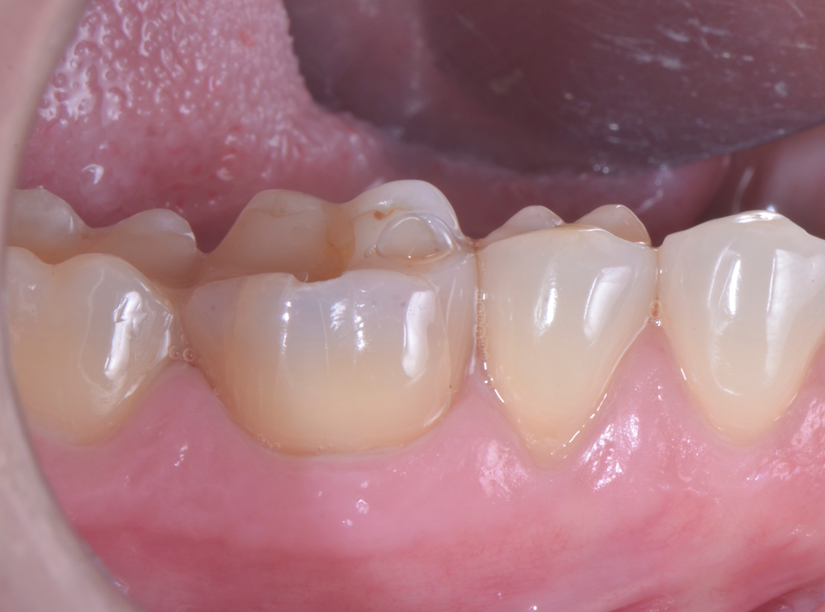

O paciente apresentou fratura vertical mésio-distal no elemento 46. Foi planejada a exodontia minimamente traumática e instalação imediata do implante Maestro Superiore (Implacil Osstem) utilizando uma guia prototipada. Após a exodontia, o implante foi instalado seguindo o protocolo de cirurgia guiada. O GAP vestibular foi preenchido com o Extra Graft. Um cicatrizador personalizado impresso com haletas facilitadoras foi capturado com resina flow e instalado. Após 30 dias, foi realizado escaneamento indireto para obtenção do perfil de emergência, utilizando protocolo digital com sobreposição do cicatrizador escaneado para confecção da coroa definitiva em zircônia policristalina estabilizada por ítria.